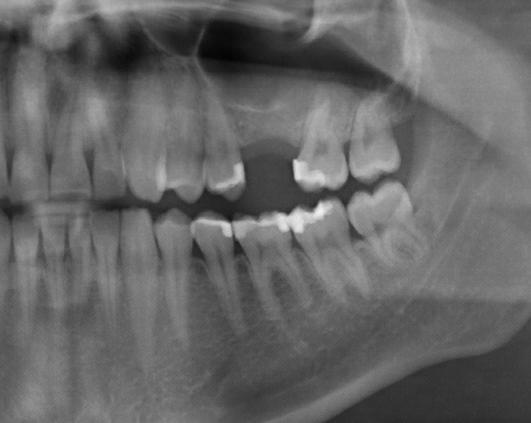

Sinus Lift With Simultaneous Implant

Sinus Lift